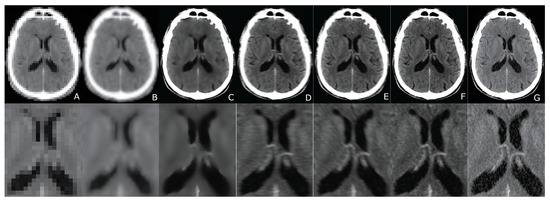

2. CT/PET Joint Sparsity

3. Computed Tomography Imaging Speeding Up

6. Evaluation

7. Results